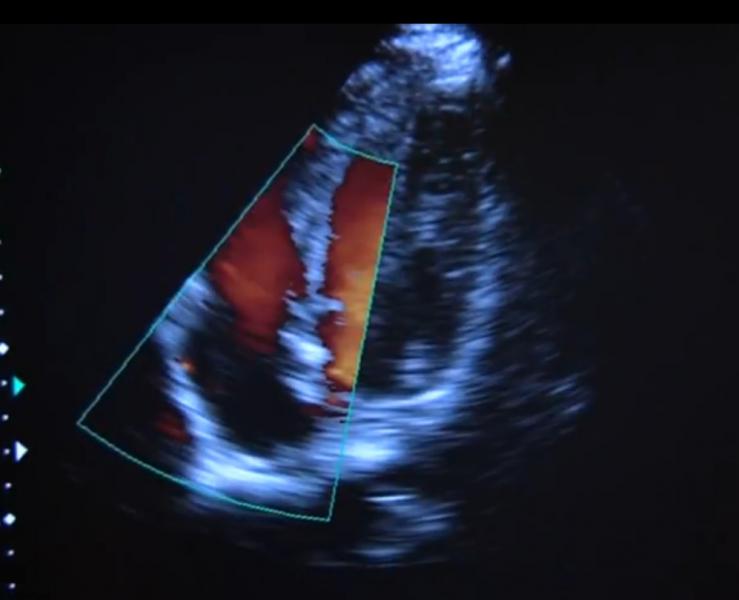

June 8, 2011 – “Jomo,” the Cincinnati Zoo & Botanical Garden’s 19-year-old silverback, western lowland gorilla underwent a cardiac ultrasound as part of a preventative study. A team of human cardiologists, technicians and corporate partners made the house call to the Cincinnati Zoo’s Gorilla World exhibit recently to perform the echocardiogram to identify any problems.

“Not only were we trying to instruct Jomo on where and how to stand, but we also had to prepare him to get used to the wand and ultrasound conductive gel touching him,” said Evans. Once the positioning behavior and wand/gel desensitization was established, Ron and the primate team brought in the zoo’s Vet Tech, Jenny Kroll, along with the zoo’s ultrasound machine to practice with actual image collection. Finally, after months of preparation, Jomo was ready for the official scan. The Christ Hospital’s team of cardiologist Wojciech Mazur, M.D., and Jennifer Schaaf, BS, RDCS, echo lab technical director, joined the Cincinnati Zoo’s team to administer the scan using a state of the art Xario XG Ultrasound system loaned to the zoo by Toshiba.

“The high quality of contrast and resolution with increased depth penetration made the Toshiba Xario XG scanner very valuable in hard-to-scan patients such as these,” said Mazur. “The Xario XG is able to uncover minute details in the differentiation of tissue and borders. The results of all gorilla echo scans are collected and can be shared with other zoos, beginning to build a norm reading for veterinarians to compare in the future.”